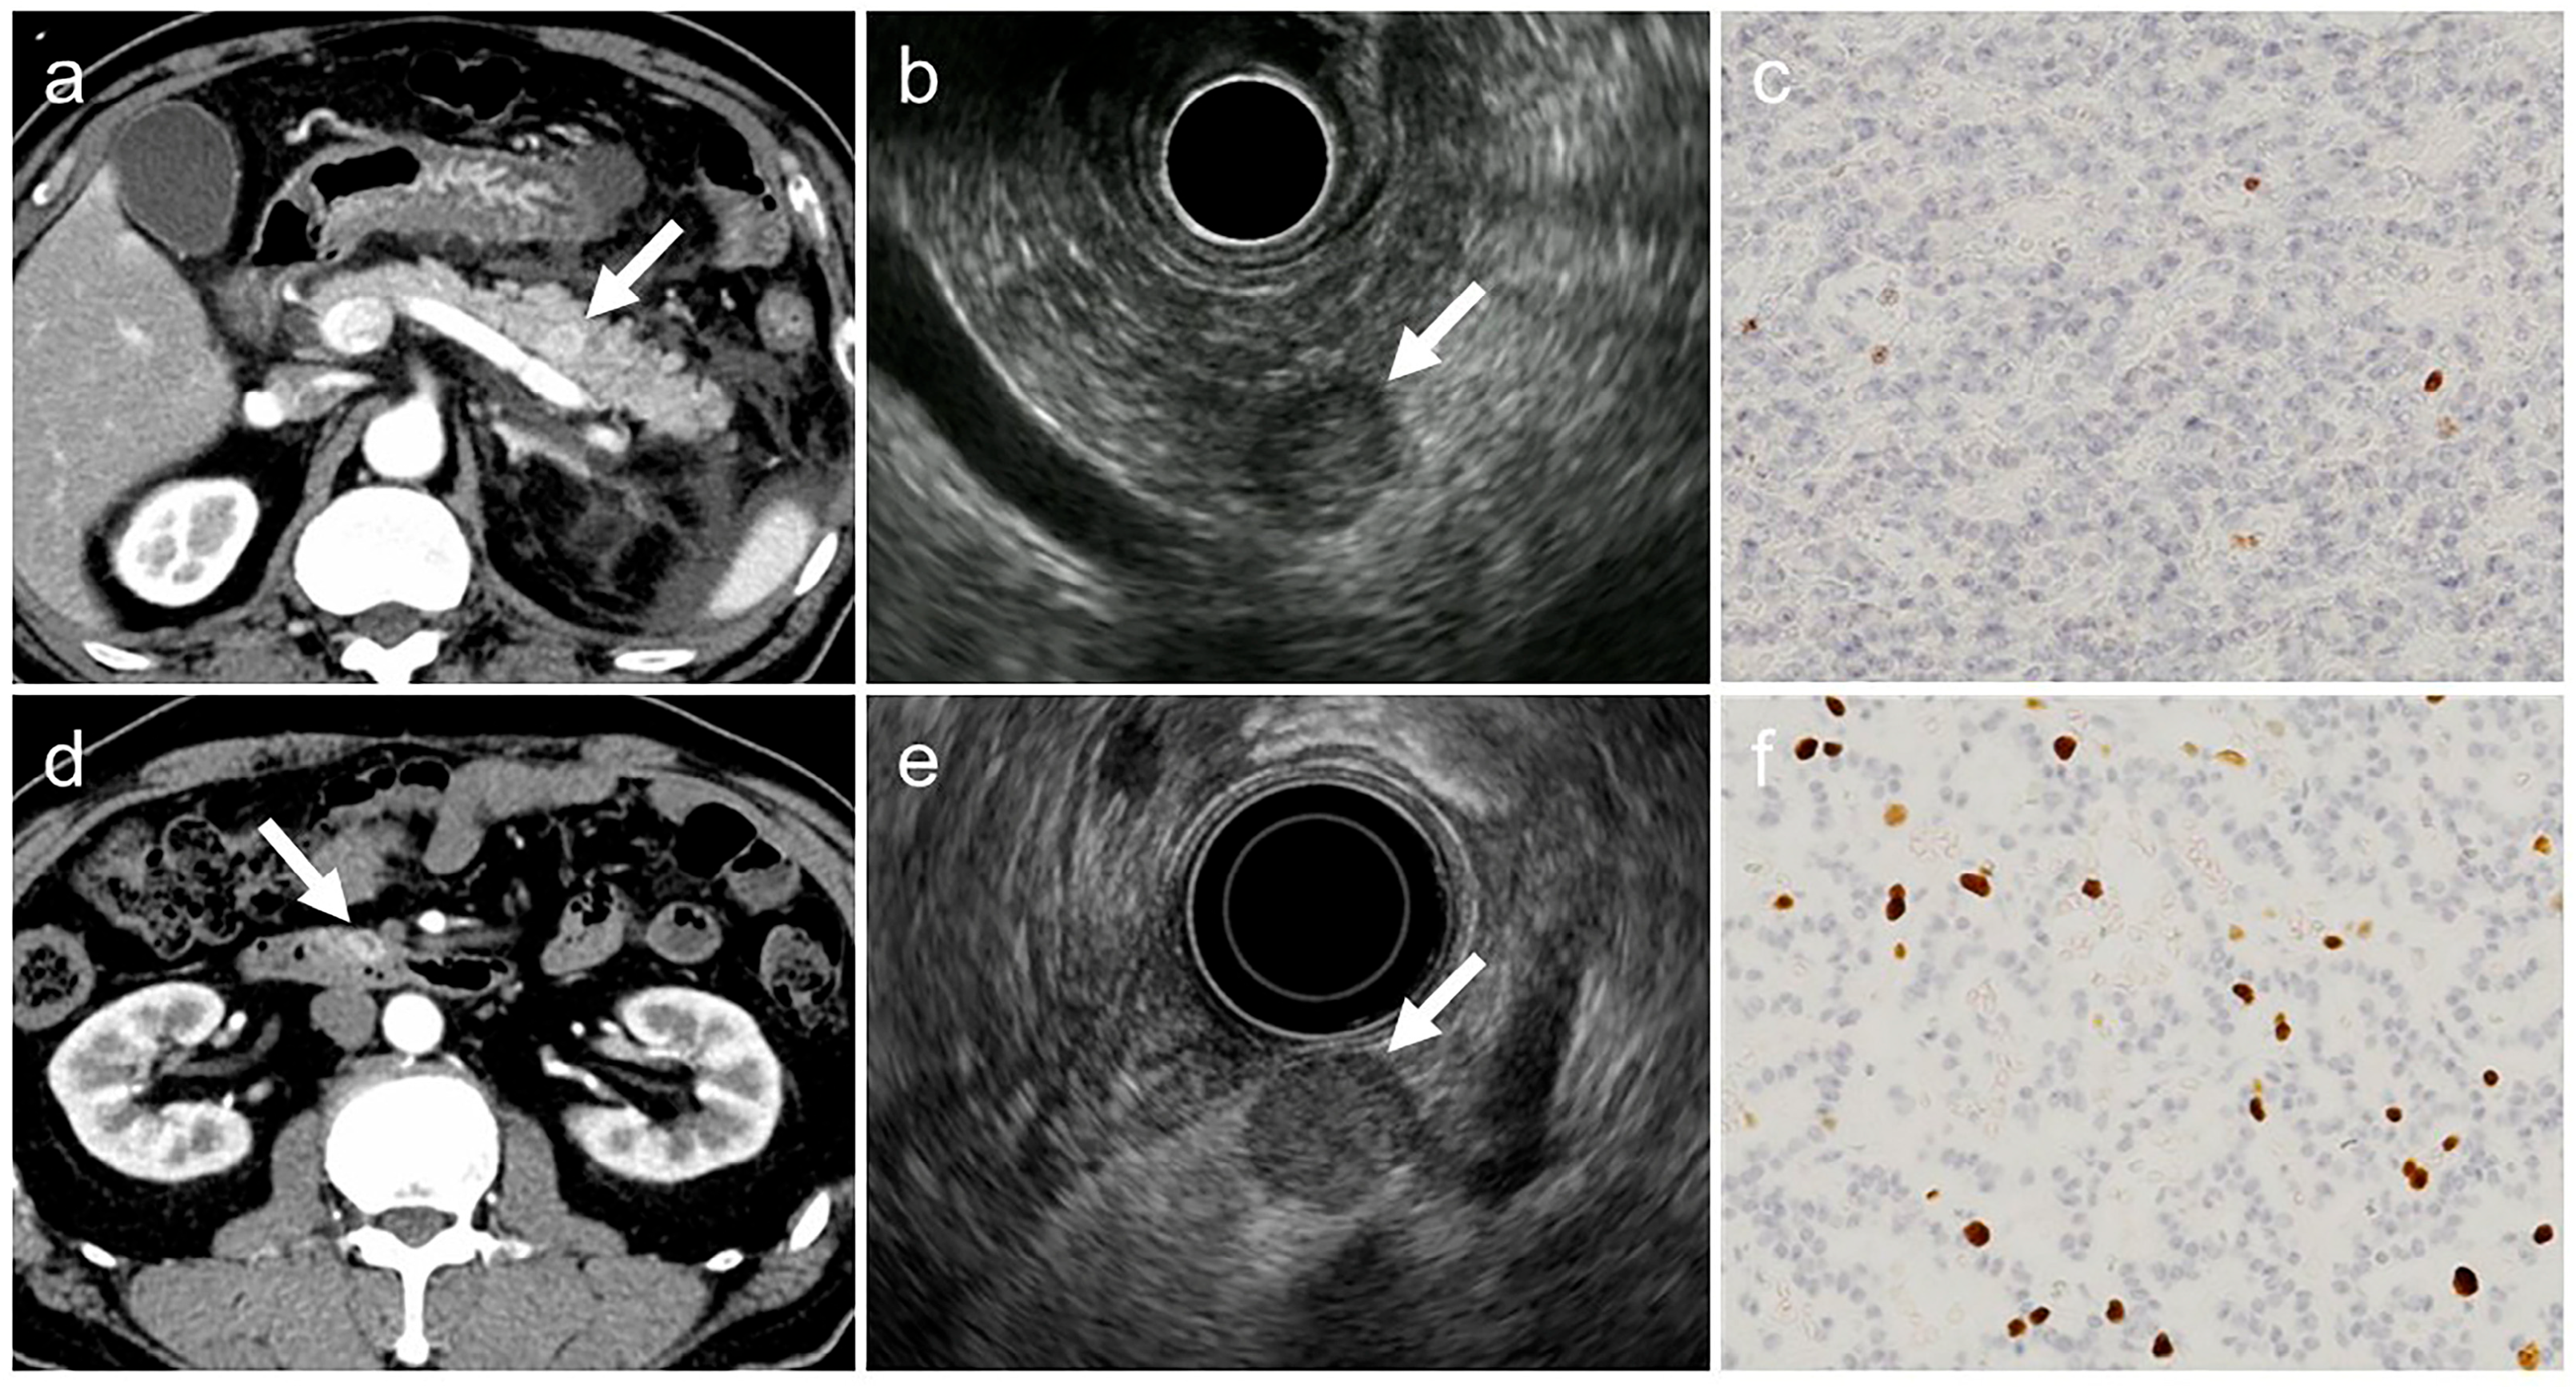

2.4. Image Analysis

- (a)

- tumor margin contour on EUS (regular or irregular),

- (b)

- internal echogenicity on EUS (homogeneous or heterogeneous),

- (c)

- arterial phase enhancement pattern on contrast-enhanced CT (presence or absence of early enhancement),

- (d)

- presence of calcifications on CT or EUS (identified as hyperechoic structures or high-attenuation areas),

- (e)

- presence of cystic degeneration on CT or EUS (non-enhancing anechoic areas),

- (f)

- main pancreatic duct (MPD) dilation (MPD diameter ≥3 mm on CT or EUS).

- Irregular tumor margins: tumors with spiculated or infiltrative borders in ≥20% of the lesion circumference.

- Heterogeneous echogenicity: tumors with internal echo variability not attributable to cystic changes or calcifications.

- Early enhancement: tumors show greater contrast enhancement than the normal pancreatic parenchyma during the arterial phase.

- Calcifications: hyperechoic areas on EUS correspond to high attenuation on non-contrast CT.

- Cystic degeneration: anechoic regions on EUS without enhancement on any contrast-enhanced CT phase.